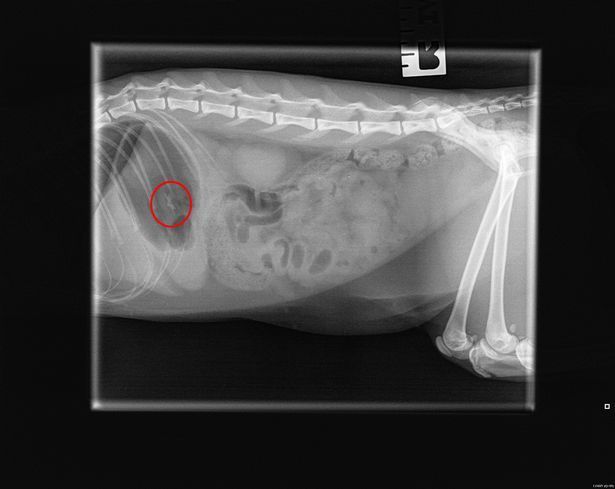

Wróćmy jednak do Zeldy. Kotkę poddano licznym testom, aby dowiedzieć się, co jej dolega. Dopiero zdjęcie rentgenowskie ujawniło, co przysparzało jej cierpienia. Co lekarz znalazł w żołądku Zeldy? Plastikową, dekoracyjną gwiazdkę wraz z nićmi bawełny o imponującej długości. Przedmioty musiały zostać usunięte chirurgicznie.